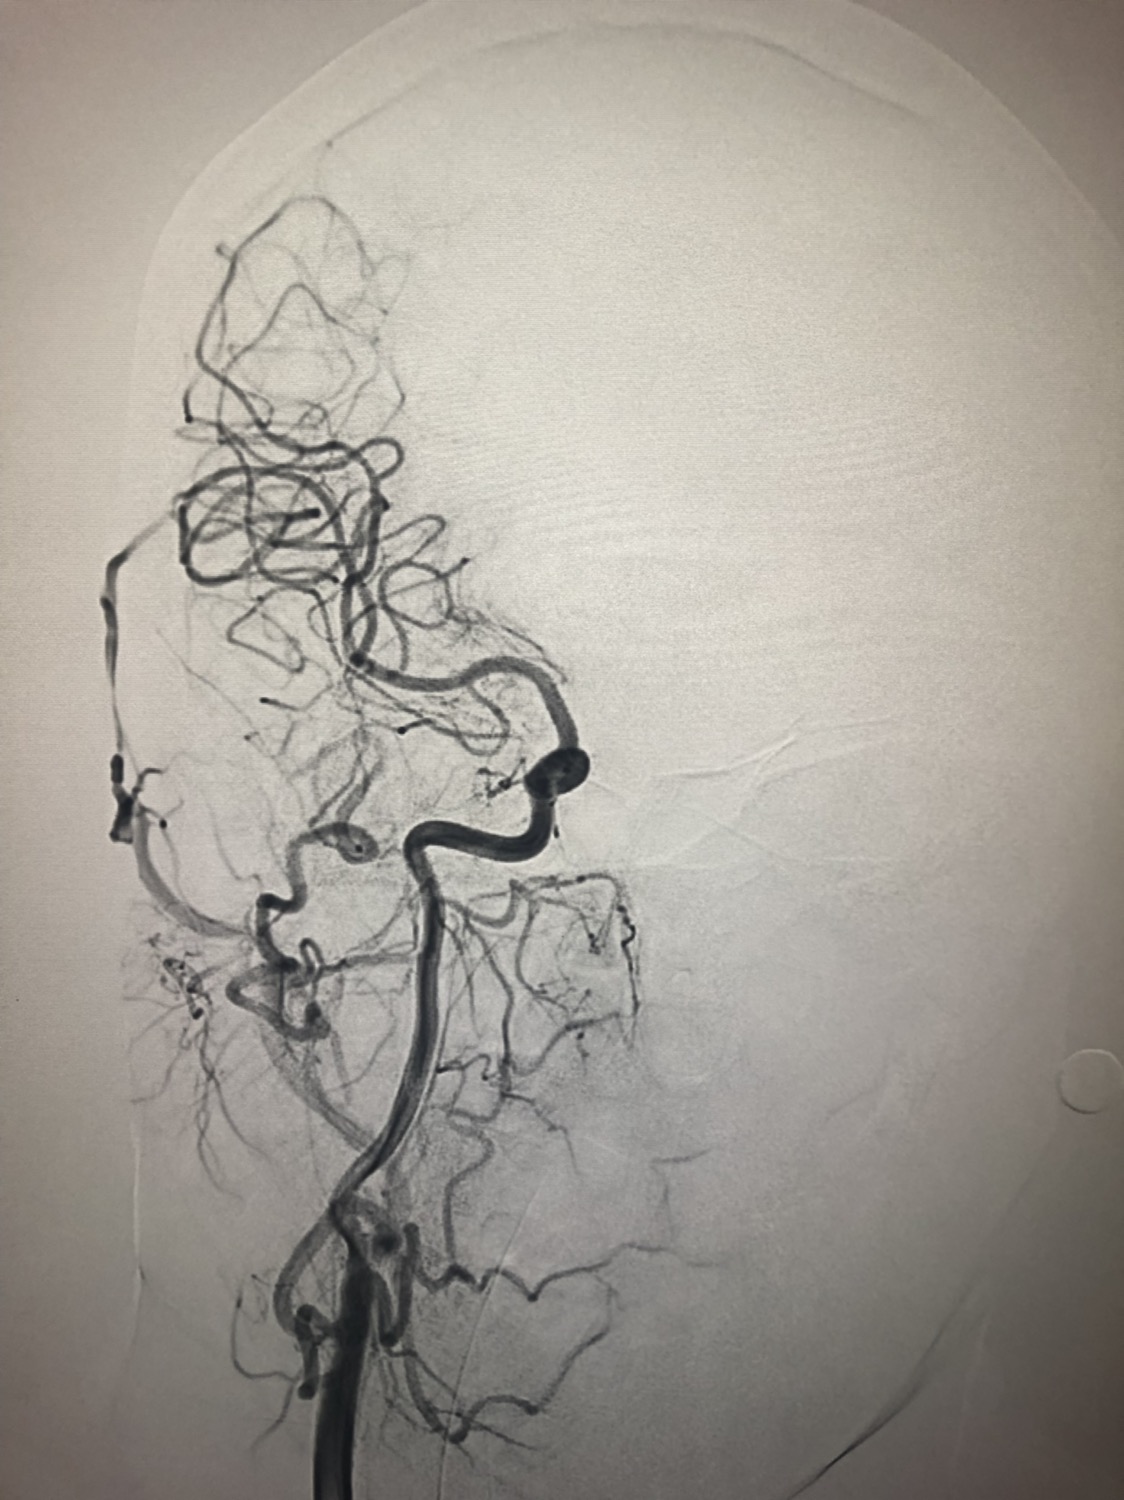

1周前房颤栓塞肱动脉,切开取栓后服用利伐沙班3天。突发偏瘫凝视3小时。上台看M3、A3血栓,国产普威森6f125cm抽吸导管高到位结合尼科3x20mm小支架,结合精细操作,m3和a3的血栓也可以轻松取出。不刺激血管。加造影射线16min两次取栓两个血管再通。

术后良好。